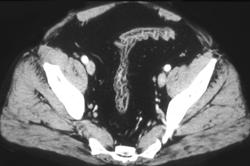

Apple Core Lesion in the Sigmoid Colon